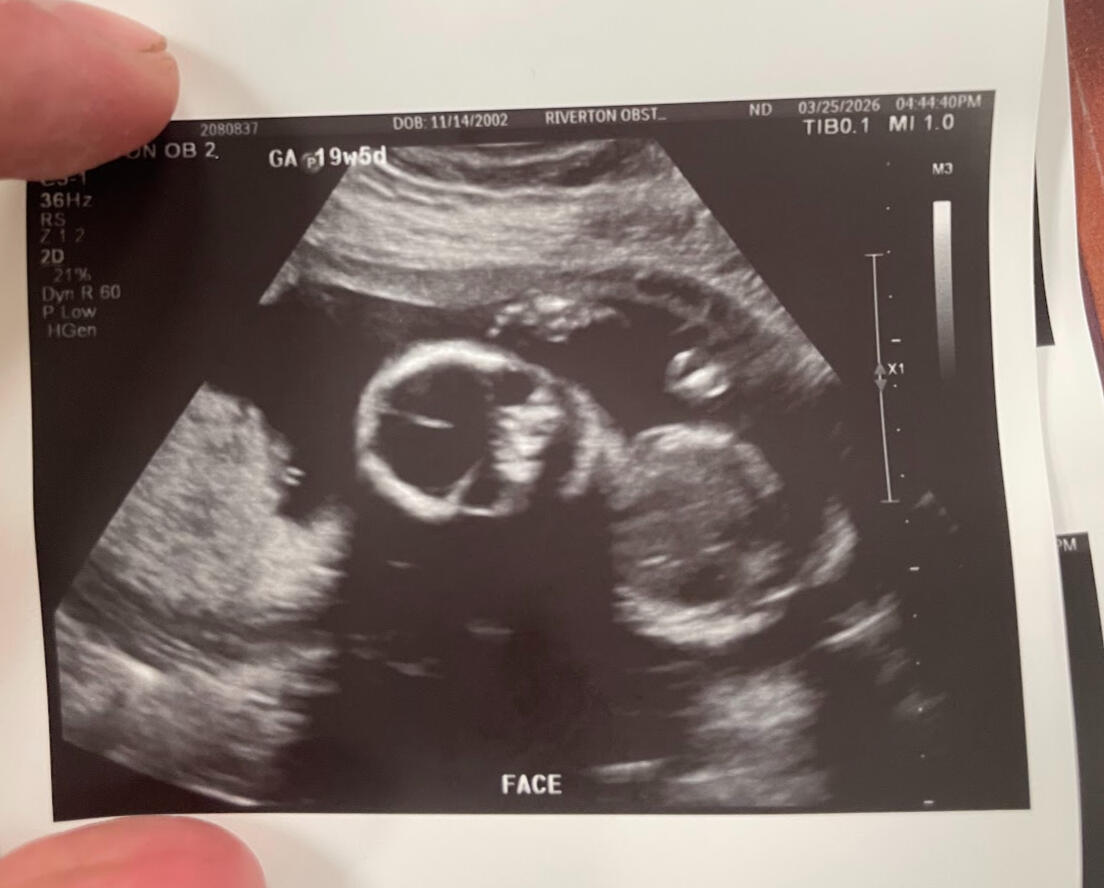

Ultra sound @ March 25th

It has only been three months and three weeks since we found out we are having a child.Since then, we have gained a bassinet in our bedroom and a closet filled with new baby clothing. New artwork for our nursery and overall has been the subject of conversation every single day since.It is sufficient to say that our lives have changed forever.Having this drastic a change in such a short time has come with much stress and complications, and almost all aspects of our lives.Most surprising are the emotional changes we have undergone over the past three months. As it turns out, (from parenting books and colleagues’) husbands and wives will go through drastic hormonal changes while the wife is pregnant.All this has led to a lot of planning for our future baby. There are times when I feel more stress than I've ever felt in my entire life.However, in the same breath, I believe I have also felt the most gratitude and love for my family that I have ever felt.For sure, things are differentBut overall, despite all the sleepless nights and worrying about our baby’s future, I’ve been able to see the world in a different, more positive light than ever before.Abree and I have been dreaming of this moment and have been planning for our new child. Now that it is here, it feels almost surrealWe are very excited